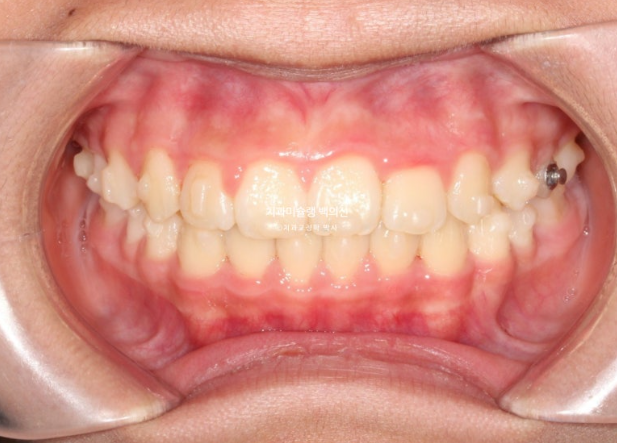

25년 5월부터 25년 7월까지 앞니배열 개선을 위해 추가장치를 짧게 낀 후 치료를 마무리 했습니다.

25.07

중심선은 잘 맞고

어금니 교합은 물샐틈 없는 1급 교합관계를 보입니다.

이제 전 후 비교해 보겠습니다.

총 치료기간은 1년 6개월이고 중간에 중심선 이슈로 잠시 쉬는 시간이 4개월 있었습니다.

재제작은 총 2회 했습니다.

24.02~25.07

치료결과가 어린이 교정이 아닌 정식 성인교정 치료 결과에 준한만큼 유지장치도 철저히 들어갑니다.

어긋난 중심선이 맞아졌으며 기울어진 앞니 치축도 좋아졌습니다.

앞니가 깊게 물리는 과개교합도 좋아졌습니다.